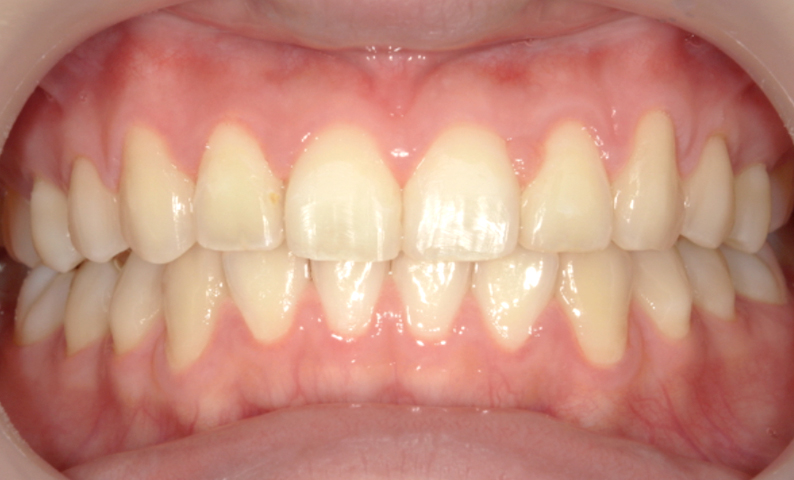

症例_001 上下顎の部分矯正

治療期間:12ヶ月金額:54万円+税女性前歯のガタガタ逆八の字

| Before | After |